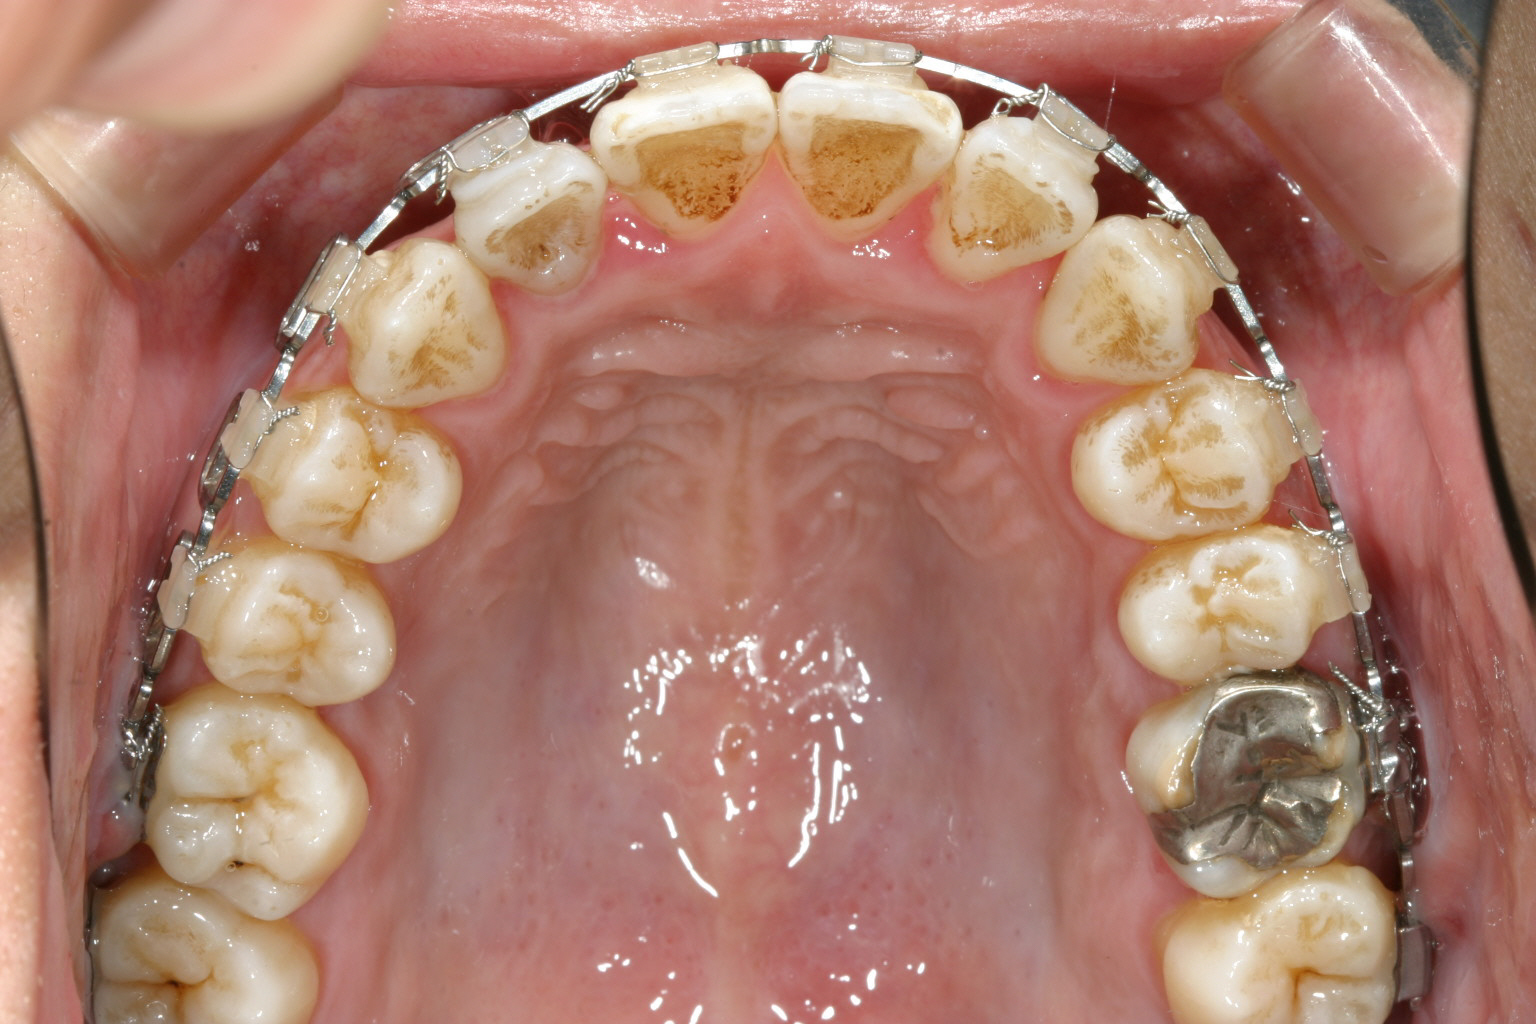

1年9カ月後です。 前回の写真よりもアーチがU字になってきているのが分かります。

下顎の綺麗なU字になりました。

今回のケースは下顎の前歯の90度回転を戻すのに難儀しました。

何度かブラケットを貼り替えてリンガルにボタンをつけゴムの力で回転を助け

やっとの事で綺麗なアーチに仕上げました。

開咬閉じるより下顎前歯を整列させる方が難しかったです。

この様な開咬ケースにはやはりマルチループワイヤーに限ります。

毎回の調整に少し手間と時間がかかりますが確実に綺麗になります。